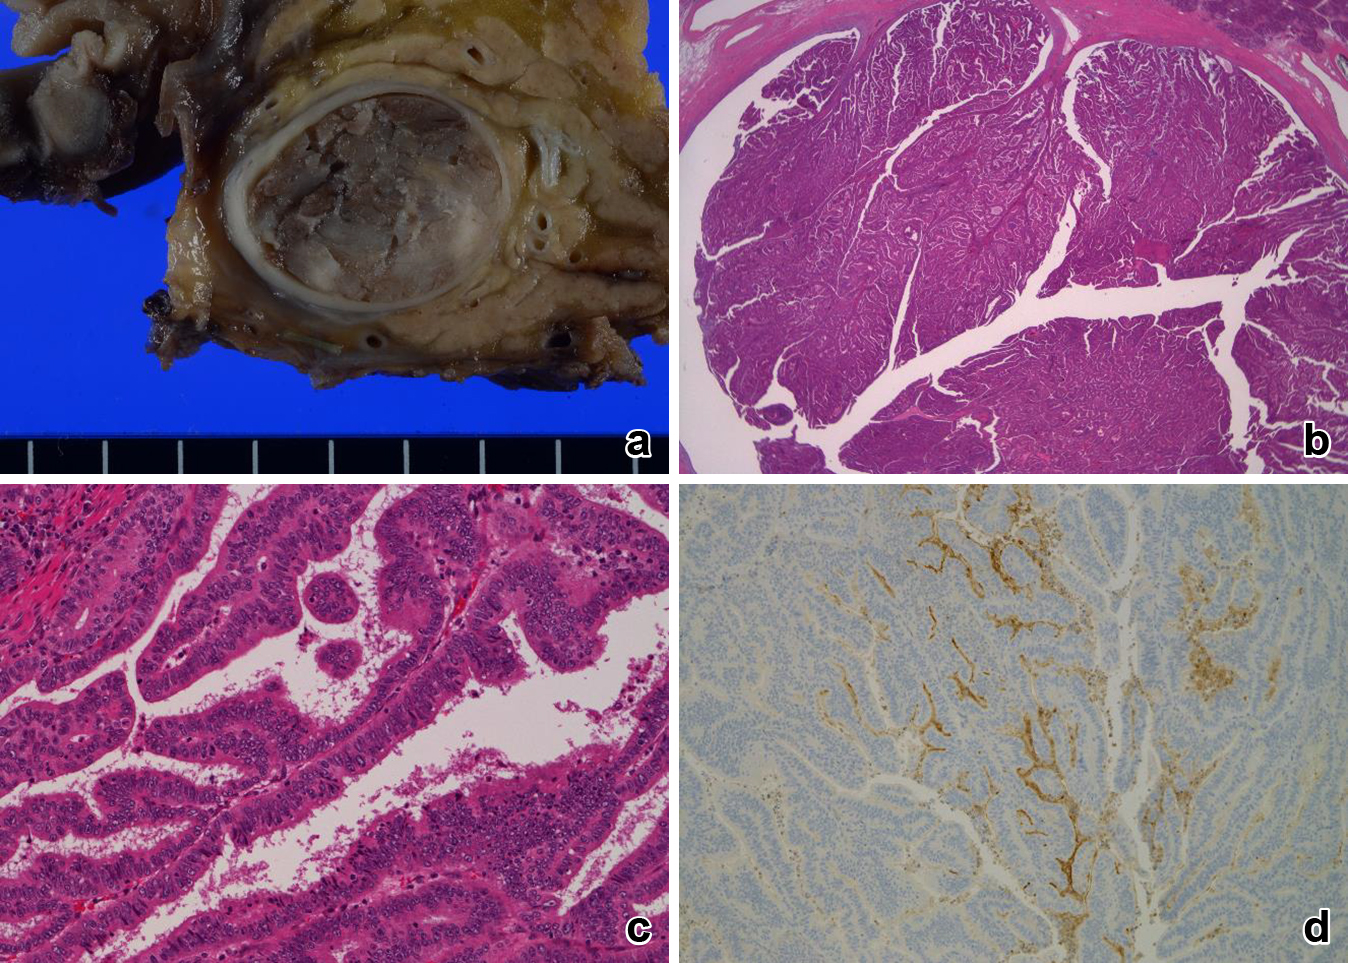

病理組織学的検査所見:肉眼的には,膵内胆管の内腔を埋めるように乳頭状に増殖する腫瘤を認めた(Fig. 7a).病理組織学的には,狭い線維血管性の間質を有する乳頭状の増殖を示しており(Fig. 7b, c),MUC1陽性(Fig. 7d),MUC5,6が陰性で,胆膵型の形質と考えられた.胆道癌取扱い規約第6版では,遠位胆管癌,乳頭膨張型,16×19 mm,pap,pTis,med,ly0,v0,ne0 pStage 0であり,2010年WHO分類ではhigh grade without invasionで胆膵型のIPNBと診断された.腫瘍の周辺に前癌病変は認めなかった.初回病変と比較すると,組織学的に類似したIPNBであり(Fig. 8b, c),MUC1陽性(Fig. 8d)およびMUC5,6陰性であることから胆膵型の同形質であった.

a) Macroscopic findings showed a papillary expansive tumor occupied in the distal bile duct. b) (HE ×1), c) (HE ×400) Microscopic findings showed a papillary neoplasm covering delicate fibrovascular stalks. d) Tumor cells were positive for MUC1 staining (second tumor).

a) Macroscopic findings showed a papillary expansive tumor occupied in the right hepatic duct. b) (HE ×1), c) (HE ×400) Microscopic findings showed a papillary neoplasm covering delicate fibrovascular stalks. d) Tumor cells were positive for MUC1 staining (first tumor).